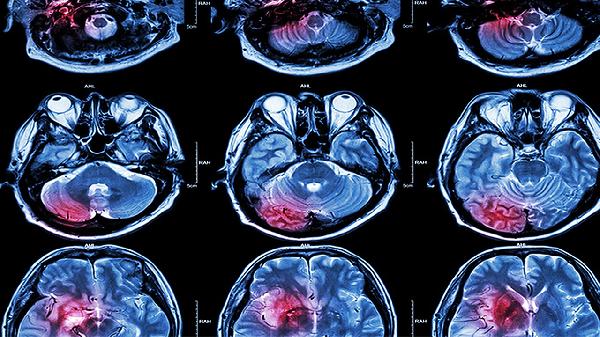

脑梗死护理诊断方法有哪些?

脑梗死护理诊断方法主要有观察意识状态、评估肢体功能、监测生命体征、检查吞咽功能、识别心理状态等。